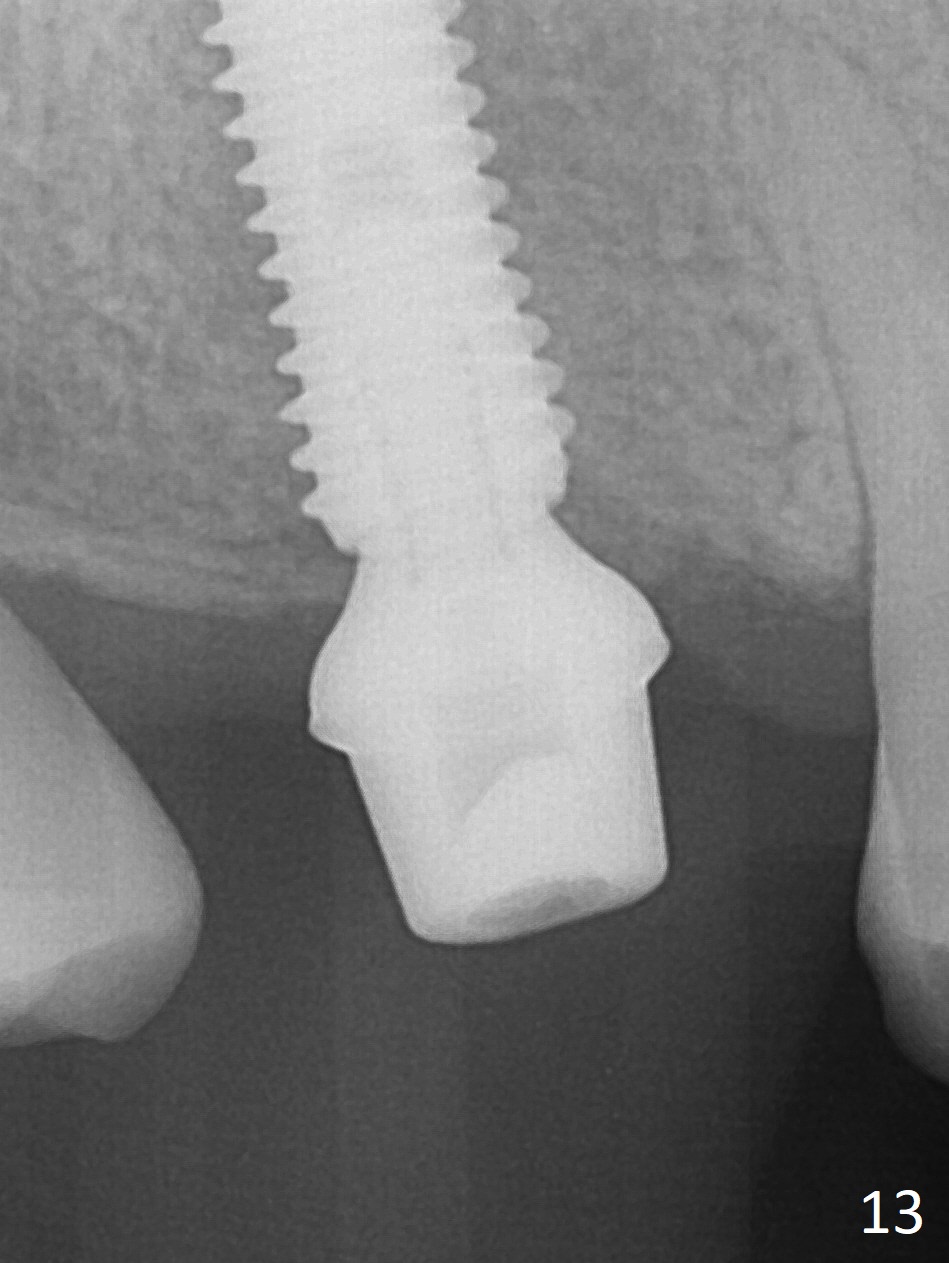

The palatal cusp of the affected 2nd premolar is apparently rotated distal (Fig.1). It is more obvious for the socket (Fig.2): the palatal (P) portion of the socket is more distal than the buccal (B) one. When the gauze is removed (Fig.3), Lindamann bur is used to remove the disto(D)palatal bone of the socket (data not shown), followed by starter drill in the DP wall obliquely (Fig.3'). Once the drill enters the bone for 1-2 mm, the bur is straightened and pushed slightly distal (Fig.3''). Fig.4 shows a parallel pin distal (overcorrect) to the original socket (Fig.4 red dashed line). Sequential osteotomy is conducted until 3.8x13 mm drill for 18 mm (Fig.5): note the 2 steps of the osteotomy (red lines). Since the apical portion of the osteotomy is larger than the drill, a larger implant than expected (5x16 mm) is placed. The implant ends up in the middle of the edentulous area (due to the stepped osteotomy; Fig.6-9; >60 Ncm). Vera allograft is placed (Fig.7-9 *) prior to and after placement of a 6.5x4(3) mm abutment (Fig.8-10). The remaining socket opening is sealed with a piece of Collagen plug (Fig.10 *). The socket is then closed by an immediate provisional (Fig.11 P). The abutment is retightened 2 months postop (Fig.12,13). The crown is cemented 4.5 months postop. Panoramic X-ray and CT are taken nearly 7 months post cementation (Fig.14,15) when the patient is ready for #30 implant guide preparation.